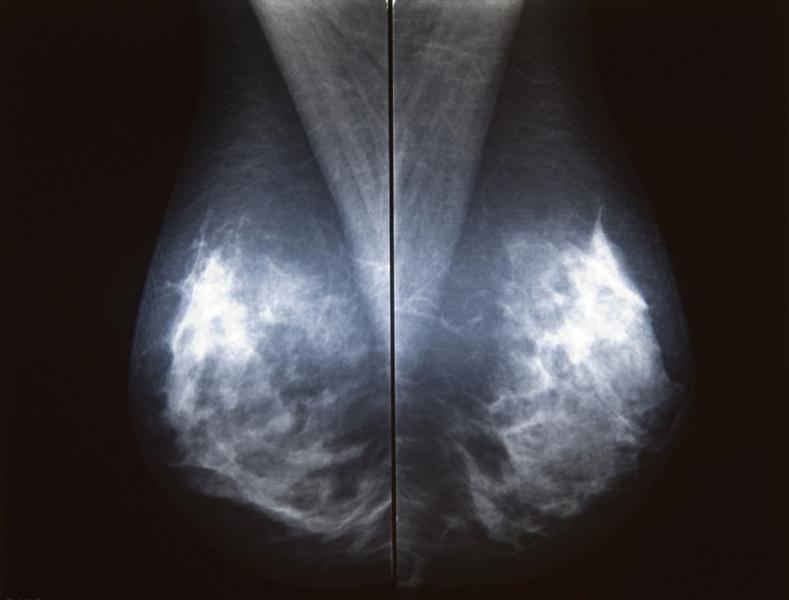

The U.S. Food and Drug Administration (FDA) recently approved two systems from Siemens Healthcare. Mammomat Fusion is the latest addition to the Siemens family of full-field digital mammography systems that offers premium product features to address the specific needs of volume screening centers and small to medium-sized hospitals. The system features a new generation cesium-iodide detector — an innovative, layered configuration of the photo diodes within the detector that enables more efficient utilization of the radiation dose. The result is a high image quality at a patient dose that is at or below the range of other full-field digital mammography systems, with an even lower dose delivered in cases where the patient’s breast thickness exceeds 50 mm. The system’s large image matrix of 23 x 30 cm makes it convenient for screening various breast sizes.